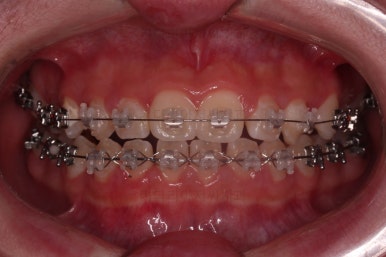

악궁확장 이 후 브라켓을 부착합니다.

이번 환자분이 선택하신 장치는 엠파워 클리어라고 하는 자가결찰 세라믹 장치인데요.

철사를 스스로(자가) 묶을 수(결찰) 있는 뚜껑이 달린 세라믹 성분의 장치입니다.

대표적인 장치가 클리피씨 장치이며 클리피는 일본회사, 동래교정치과 키다리아저씨치과가 쓰는 엠파워는 미국회사라는 차이가 있고 큰 틀에서는 동일한 계열의 장치입니다.

틈이 다 모였고 교합도 많이 좋아졌죠?

끝내도 될까요?

일부러 힘을 뺐다가 느슨하게 해보았다가 틈새가 다시 안벌어지는지를 충분히 확인한 후 치료를 종료하게 됩니다.

그래서 적극적인 치료는 진작에 끝났다 하더라도 치료 말미에 기다리는 시간이 많이 소요되는 치료가 이번 치료입니다.

안정성을 충분히 확인한 뒤 치료를 종료합니다.

전후 사진을 비교해 볼게요.

악궁확장을 통해 위아래 악궁의 크기 조화를 맞췄고, 틈새도 모았으며 교합도 적절히 마무리를 했습니다.